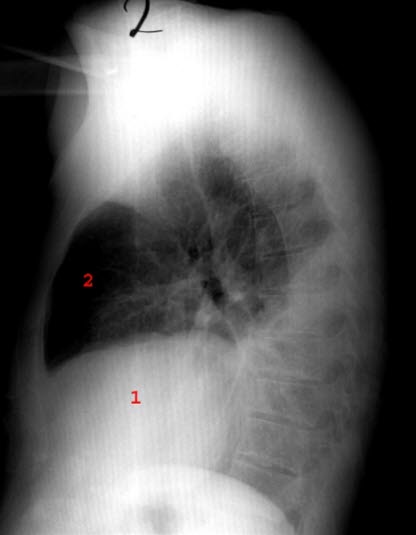

Pleuropneumoni - side

Pneumoni med pleuravæske